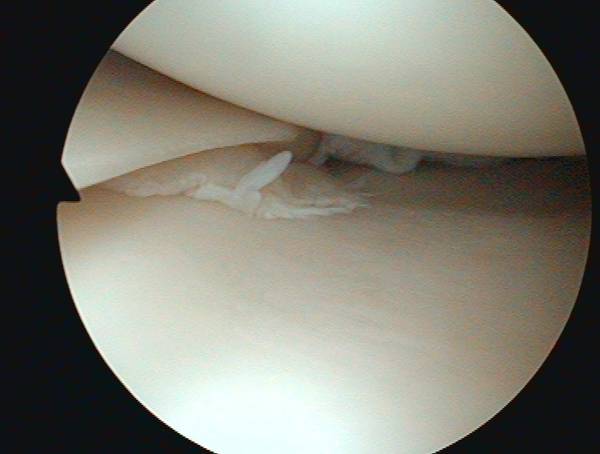

eingerissener Meniskus

Bei kompletten Einrissen, verschobenem Meniskusgewebe, Gelenkblockierungen, anhaltenden Beschwerden oder Funktionseinschränkungen ist eine Gelenkspiegelung (Arthroskopie) des Kniegelenkes notwendig. Der defekte Meniskus kann dann zum einen seine ursprüngliche Pufferfunktion nicht mehr wahrnehmen, und zum anderen schädigt das eingerissene Meniskusgewebe den umliegenden Gelenkknorpel und führt somit zu einem vorzeitigen Gelenkverschleiß.

Die Therapie besteht in der arthroskopischen Entfernung des eingerissenen Meniskusanteils (Meniskusteilentfernung) . Der Eingriff kann problemlos ambulant durchgeführt werden. Eine Vollbelastung des Kniegelenkes ist nach ca. 2-3 Tagen möglich. Bürotätigkeiten können bereits nach einigen Tagen wieder ausgeübt werden.